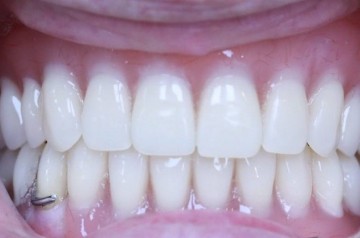

Пациентка, 49 лет. Жалобы частичное отсутствие зубов. Проведено, лечение, удаление несостоятельных зубов, установлены импланты, протезирование коронками из диоксида циркония.